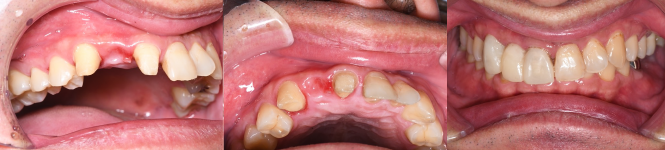

症例3. 歯肉切除

![]() |

|

| 歯茎が部分的に分厚い状態です。 | 歯茎の位置を下げました。 | これで精度が高くかつ維持力の高い被せ物ができます。 |